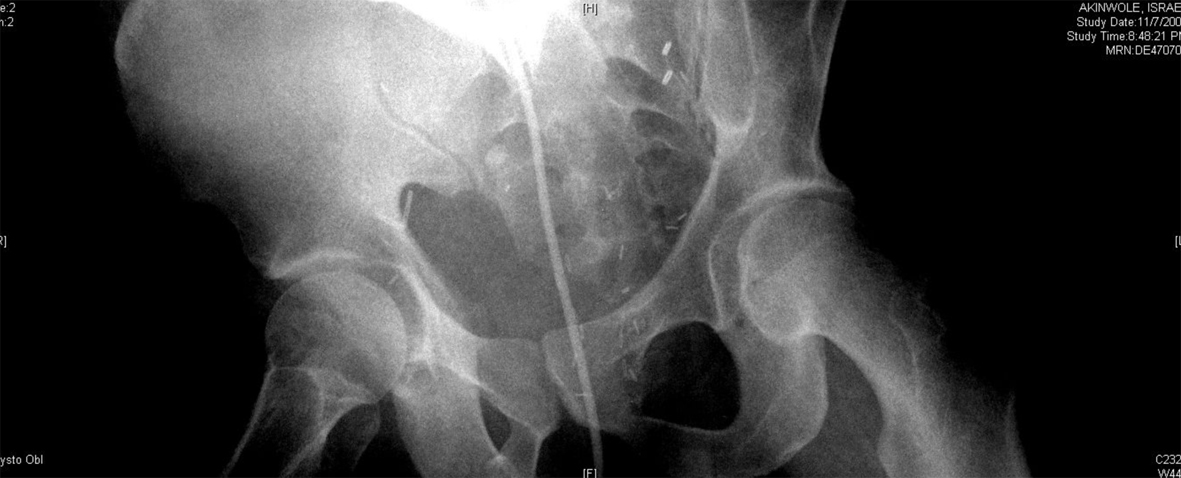

A 54-year-old African American male, presented to our facility with a prostate specific antigen (PSA) of 5.8 ng/mL. Prostate biopsy revealed three cores of Gleason 6 adenocarcinoma. On digital rectal examination he was found to have an approximately 60 g prostate, which was firm and smooth. He underwent an open retropubic radical prostatectomy (RRP). The pathologic specimen showed Gleason 7 adenocarcinoma occupying 20% of the specimen. The stage was T1cN0M0. On the fourth post-operative day, the patient presented to the Emergency Department in another facility complaining of chest pain and shortness of breath. A clinical diagnosis of pulmonary embolism (PE) was made and he was treated with a full dose of IV heparin. He subsequently developed hematuria and complained of lower abdominal pain. On physical exam, he was found to be pale, with diffuse abdominal tenderness, guarding and tachycardia. The patient was then transferred to the Surgical Intensive Care Unit (SICU) at our facility. He received two units of packed red cells. A cystogram showed complete disruption of the UVA with displacement of the bladder neck in the left upper quadrant of the abdomen producing a “pie in the sky” appearance. However, there was no evidence of urinary extravasation indicating an intact bladder neck (Fig. 1, 2). A CT scan revealed a very large pelvic hematoma displacing the bladder neck towards the left upper quadrant (Fig. 3). An IVC filter was inserted to prevent migration of thrombi so that he could discontinue the use of anticoagulants. Patient was managed conservatively for 6 - 8 weeks with gentle traction, and this helped maintaining the bladder neck within the pelvis. A cystogram showed no extravasation of urine. The Foley catheter was removed. The patient voided well initially; however, he developed bladder neck contracture (BNC) after 2 weeks. He was managed with dilation of the bladder neck, but the bladder neck did not return to the pelvis. It was found to be 2 cm away from the urethra, and a “pseudo-tunnel” made of scar tissue was seen between the true bladder neck and the membranous urethra. A surgical approach was used to explore the patient and the “pseudo-tunnel” was resected. Re-anastomosis of the bladder neck with the urethra was performed. The patient has remained continent since then and voids with minimal post void residual urine. There has been no recurrence of BNC (Fig. 4, 5). He needs intra-cavernous injections to help with erections. His post-operative PSA has remained undetectable.

![]() Click for large image | Figure 2. Showing significant displacement of the bladder neck (oblique view). |